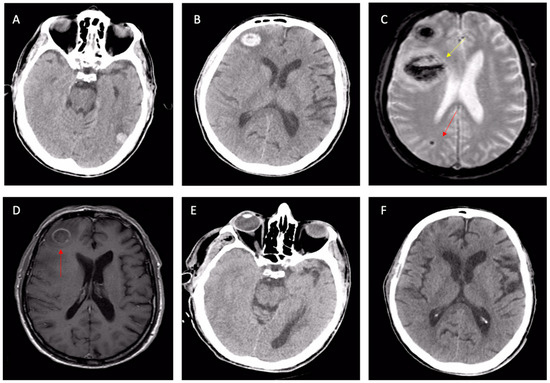

2.3. Diagnosis of CAA

- Charidimou, A.; Boulouis, G.; Frosch, M.P.; Baron, J.C.; Pasi, M.; Albucher, J.F.; Banerjee, G.; Barbato, C.; Bonneville, F.; Brandner, S.; et al. The Boston criteria version 2.0 for cerebral amyloid angiopathy: A multicentre, retrospective, MRI-neuropathology diagnostic accuracy study. Lancet Neurol. 2022, 21, 714–725. [Google Scholar] [CrossRef]

| Lobar ICH | Sudden Onset of Headache, Focal Neurological Signs, Seizures, or Altered State of Consciousness. |

| Cognitive impairment | Cognitive impairment not otherwise explained. Three possible variants: gradual, stepped, or rapidly progressive (expression of a greater inflammatory component). |

| Inflammatory forms | Subacute or rapidly progressive cognitive decline; possible epileptic manifestations. Susceptible to anti-inflammatory therapy response. Sometimes associated with TIA-LIKE presentations. |

| TFNEs (transient focal neurological episodes) | Recurrent and often stereotyped episodes of focal deficits (paresthesia, hyposthenia, aphasia) of variable duration between a few seconds and a few minutes. They often represent the clinical manifestation of subarachnoid hemorrhages. Brain CT can be negative. They can be interpreted as TIA and they could lead to the dangerous prescription of anticoagulant or antiplatelet therapy. |